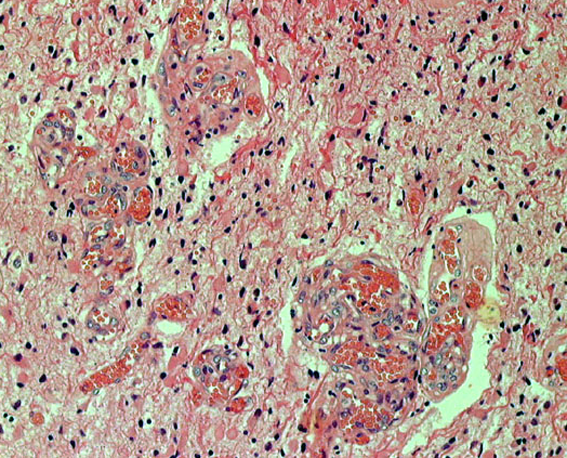

HE染色では,perinuclear haloをもった小型の腫瘍細胞が見られ,また右ではminigemistcyteと呼ばれる小さいけれどeoginophiricな胞体の豊かな腫瘍細胞の出現があり,典型的な乏突起膠腫の像です。

左に細かい石灰化が見られます。右は,グレード2の乏突起膠腫には珍しい血管内皮の増生 gromerulation なのですが,必ずしも悪性像とはいえません。通常の乏突起膠腫と同様にchicken wireと呼ばれるような細かい腫瘍血管網も存在しました。